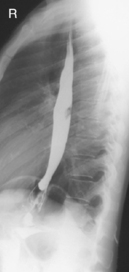

Fig. 9-31 AP supine Trendelenburg, upper GI (stomach) (Trendelenburg position best demonstrates hiatal hernia).